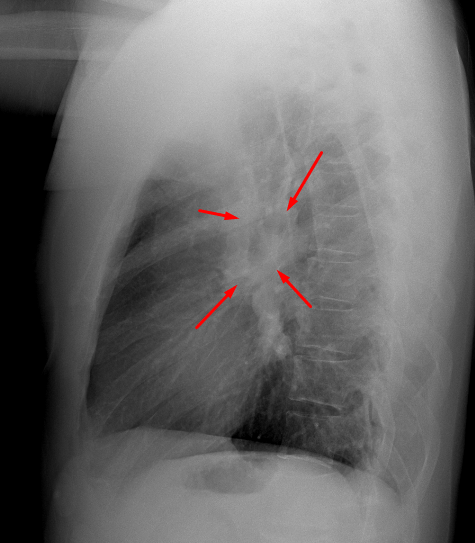

Age: 43

Sex: Male

Indication: Chest pain

Sample ReportBilateral hilar soft tissue prominence is suspicious for lymphadenopathy which could relate to neoplastic disease or systemic granulomatous disease such as sarcoidosis. Consider chest CT for further evaluation.

Otherwise, no evidence of acute cardiopulmonary disease.